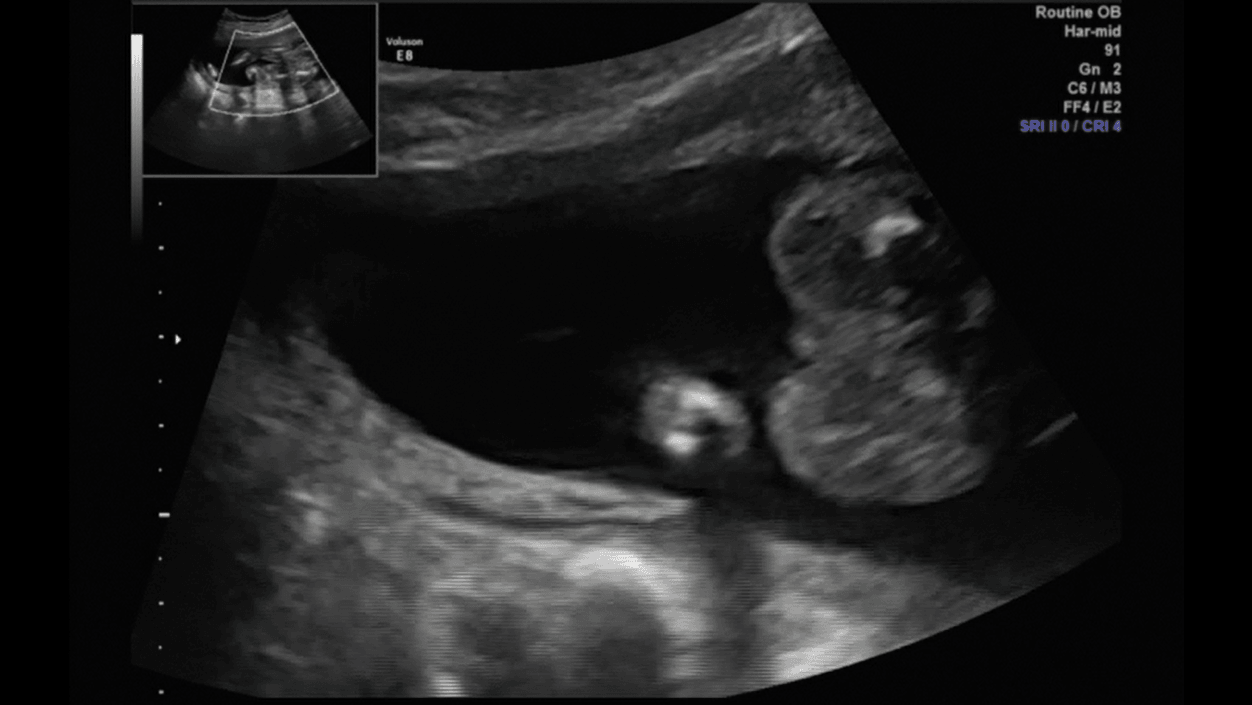

Porobiłam trochę screanów z usg połówkowego, więc pomyślałam, że wrzucę, mam nadzieję, że nie maci mi za złe ilości :D

Nóżka [emoji4]

1.png